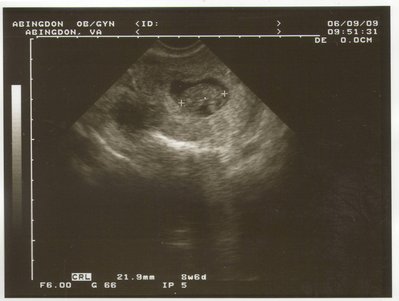

Татиана писал(а): Ой, ну как сказать: когда я своего ребенка увидела в 8 недель с ручками и ножками и сердебиением-то рыдала. А в 17- я уже делала 3д фотки: там человечек с личиком и щечками. Мне даже было страшно подумать, если что пойдет не так. в 8 недель? у меня, наверное, нет воображения совершенно... мож, поэтому и не рыдала Natiii, махнемся? я так мальччика хотела, а УЗИ показало девочку.

| Вложения: |

BabysFirstPic.JPG [ 316.26 КБ | Просмотров: 2551 ]

Похоже, и у меня воображение отсутствует  Я вот тоже удивилась, как в 8 недель Татьяна ручки-ножки умудрилась рассмотреть  Мы в 8 недель делали - да, серцебиение увидели, но никакие части тела и близко определить невозможно было... на этом сроке размер плода не больше 2 см. Ань, а эта фотка на каком сроке?

Хочу поделится фото моего малыша! Удивительно- он говорит ХАЙ всему миру. 13 недель срока